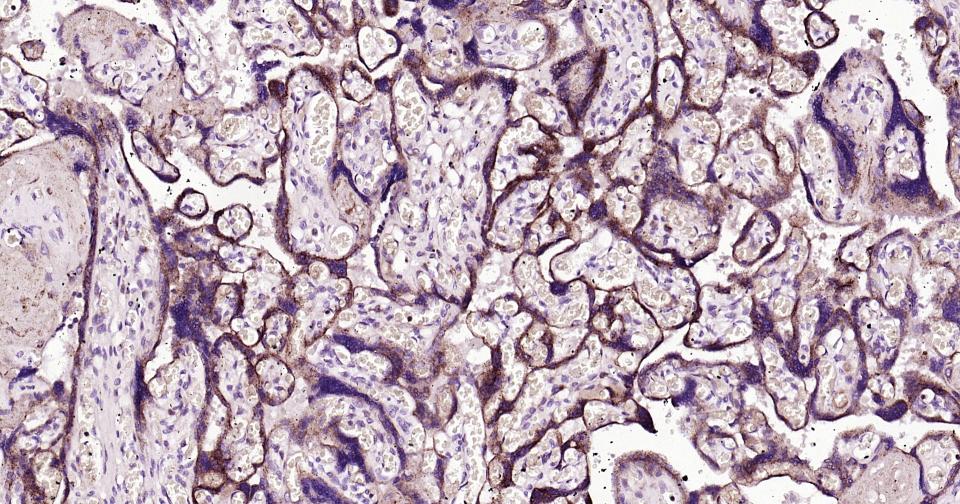

Paraformaldehyde-fixed, paraffin embedded Human placenta;Antigen retrieval by boiling in sodium citrate buffer (pH6.0) for 15 min; Antibody incubation with LAMP2 Monoclonal Antibody, Unconjugated (bsm-61207R) at 1:200 overnight at 4°C, followed by conjugation to the bs-0295G-HRP and DAB (C-0010) staining.